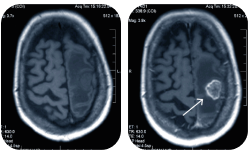

Во время исследования компьютерный томограф делает 360 снимков в трех плоскостях. Чтобы изучить их

и выявить патологию — врачу нужно время. Спешка может стать причиной неверной трактовки аномалии и, как следствие, неправильного диагноза.

Врач назначит исследование в зависимости от конкретной клинической ситуации. КТ покажет костные структуры, а МРТ — мягкие ткани. Есть ограничения и по весу. МРТ можно сделать пациентам с массой до 120-130 килограмм, а КТ пациентам с массой до 180 килограмм.